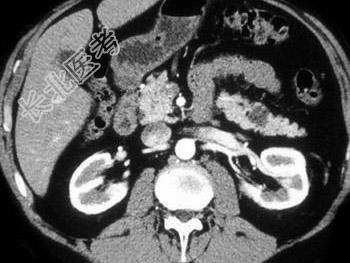

- 单项选择题对于胰尾病灶,结合图像, 最可能的诊断是 ( )

A、腺癌

B、转移癌

C、假性囊肿

D、胰腺粘液性囊腺瘤

E、脂肪瘤